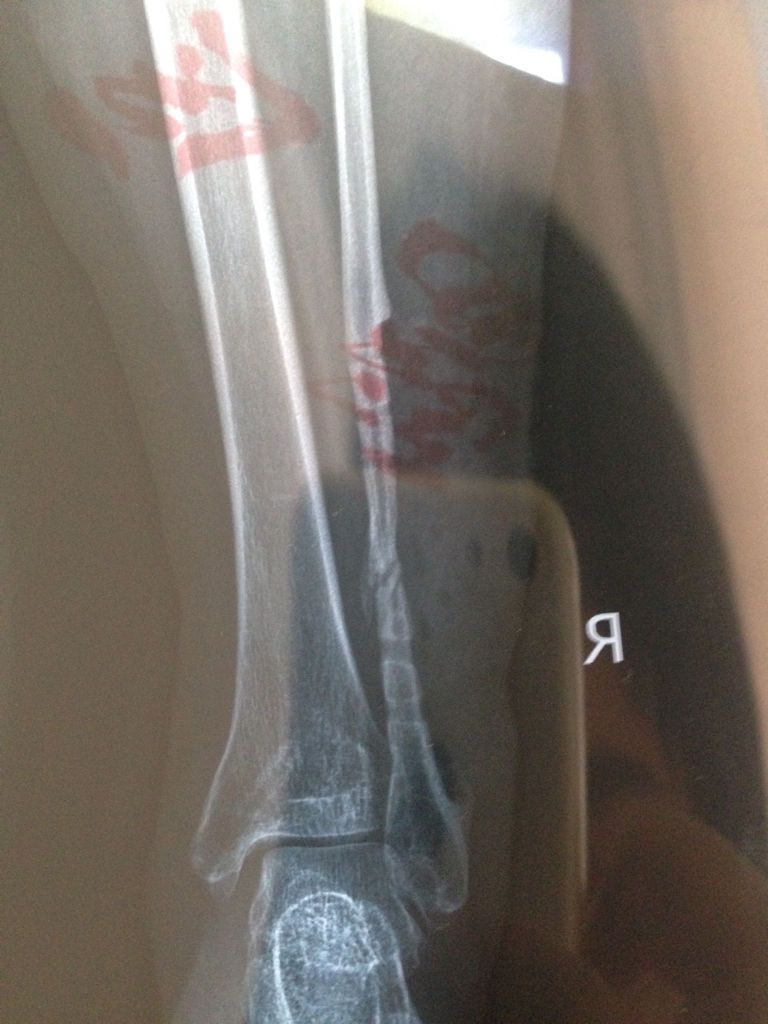

腓骨不愈合 我今年34岁,十九个月前腓骨骨折,做了内固定,现在骨折端硬化了,骨腔大部分闭塞了,前几 腓骨不愈合 我今年34岁,十九个月前腓骨骨折,做了内固定,现在骨折端硬化了,骨腔大部分闭塞了,前几天把钢板拆出来了,医生说不拆也不能好了,拆出来看看能不能通过骨膜成骨,有朋友能给个好建议我么?现在这种情况要怎样处理最好? 点击展开 匿名用户 2015-08-21 10:26 满意回答 我它助考虑十有八九是手术时骨唤认膜剥离过多,重新打通骨髓腔怪逝且,再长吧! 匿名用户 2015-08-21 10:33 宝宝知道提示您:回答为网友贡献,仅供参考。 为您推荐: 其他回答 拆了~安心躺床上养个月把~就好了 匿名用户 2015-08-21 10:30 相关问题 腓骨远端骨折已4个多月,骨折已愈合 但现在仍不能正常… 腓骨骨折 之前恢复很好 术后七个月后鼓起一包裂开并伴有脓液流出 久不愈合 左股骨颈骨折九个月愈合后多久可以脱拐?45

腓骨不愈合 我今年34岁,十九个月前腓骨骨折,做了内固定,现在骨折端硬化了,骨腔大部分闭塞了,前几天把钢板拆出来了,医生说不拆也不能好了,拆出来看看能不能通过骨膜成骨,有朋友能给个好建议我么?现在这种情况要怎样处理最好?